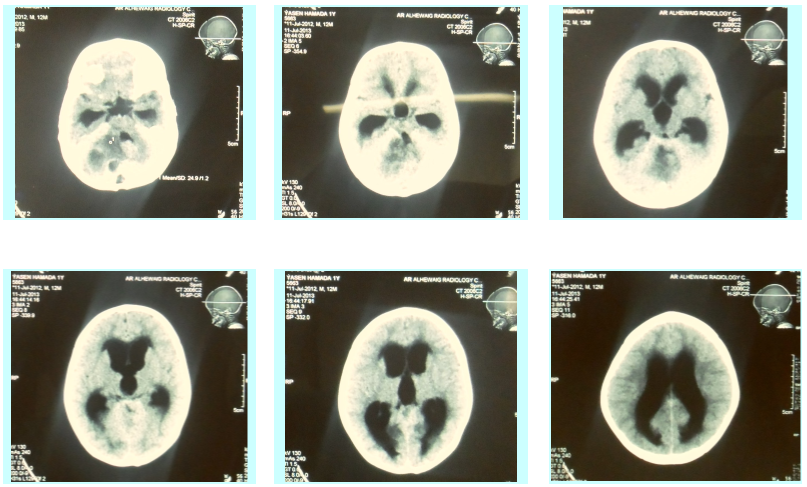

A retrospective and prospective study was carried out on twenty-one children who had hydrocephalus. An ETV was done for them using the (Karl Storz) neuroendoscopy between April 2012 and September 2014. All of them had an aqueductal stenosis. Follow- up CT was done for all children, one month and one year after the procedure.

Their age ranged from 6 months to just below two years, with the mean age was 14.5 ± 5.2 months. They were 15 males and six females. The overall success rate was 66.6% with the mean follow-up period of 18 months. VP shunt was inserted in 5 babies due to the ETV failure, one case of CSF leak and one case died due to intracranial hemorrhage.